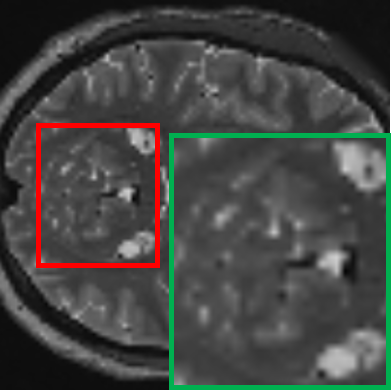

Table II provides a visual comparison of 7T-like MRI generated by various State-Of-The-Art (SOTA) SR methods using 1.5T MRI as input. The compared methods include ESRGAN [43], SR3 [26], and our proposed baseline (teacher) model. To facilitate a focused and intuitive assessment, the cerebellar region, known for its intricate structure and HR requirements, is specifically selected for comparison. To comprehensively evaluate the methods, T1w and T2w slices from both the axial and coronal planes are displayed in an alternating interleaved format, which highlights each method’s effectiveness across distinct anatomical views and tissue contrasts, allowing for a clearer assessment of their ability to capture fine structural details. The comparison reveals that ESRGAN enhances the resolution but introduces significant artifacts, where unnatural patterns distort the anatomical structures. While it provides some sharpening, the output deviates substantially from the ground truth. SR3, on the other hand, prioritizes smoothness, leading to blurred outputs that fail to recover fine details and textures, which results in a loss of critical anatomical information. In contrast, the proposed teacher model excels in preserving fine structural details and reconstructs intricate anatomical features without introducing artefacts or excessive blurring, demonstrating superior performance compared to ESRGAN and SR3 in both visual quality and alignment with the 7T ground truth. Additionally, the comparison highlights a consistent discrepancy in SR performance between T1w and T2w images. T2w images generally exhibit inferior reconstruction quality, which can be attributed to their inherently lower SNR and higher susceptibility to magnetic field inhomogeneities. These characteristics pose significant challenges for SR models, making accurate reconstruction more difficult. Despite these challenges, our proposed model consistently outperforms ESRGAN and SR3, delivering superior results for both T1w and T2w imaging.

TABLE II: Qualitative visualization comparison with SOTA models

Input (1.5T) Ground Truth (7T) ESRGAN SR3 Ours (Teacher)

T1w

[Uncaptioned image] [Uncaptioned image] [Uncaptioned image] [Uncaptioned image] [Uncaptioned image]

T2w

In one case, for a patient with partial seizures and secondary generalization, an initial diagnosis using 1.5T MRI revealed a mild volume loss in the left hippocampus, further imaging with 3T MRI was recommended to confirm the diagnosis. As shown in Table VI, the green boxes highlight the hippocampus region, while the red arrows point to areas indicative of water content within the hippocampus. In the 1.5T MRI, the patient’s hippocampal asymmetry can be appreciated with large sulci with water content on the left side (right sub-image), suggesting mesial temporal lobe atrophy. This observation was confirmed more clearly in the subsequent 3T MRI, which provided a sharper depiction of the sulcal enlargement in the same region, reinforcing the diagnosis of mesial temporal disease. Notably, by applying our student model to perform SR on the 1.5T MRI, the resulting 3T-like MRI closely resembled the actual 3T MRI. The obtained image not only improved the clarity of the hippocampal structure but also effectively captured the increased water content in the left hippocampus, closely matching the pathology observed in the 3T MRI, which underscores the clinical potential of our super-resolution framework in enhancing diagnostic capabilities. By applying our student model to super-resolve the 1.5T MRI to a 3T-like resolution, the resulting image closely resembled the actual 3T MRI. The 1.5T-based SR image not only improved the clarity of the hippocampal structure but also effectively captured the increased water content in the left hippocampus, closely matching the pathology observed in the 3T MRI.

TABLE VII: Clinical evaluation for MS case

Real 3T MRI Real 7T MRI 7T-like SR MRI (3T to 7T)

[Uncaptioned image] [Uncaptioned image] [Uncaptioned image]

In another case involving a patient with multiple sclerosis (MS), characterized by periventricular and subcortical white matter abnormalities. MS lesions, often appearing as small “dark holes” in the brain on T1w MRI, are notoriously difficult to identify on lower-field MRIs. As shown in Table VII, the real 7T MRI provided a significant improvement in resolution compared to the 3T MRI, enabling clearer visualization of MS-related changes in the periventricular regions, which highlights the importance of 7T MRI in detecting subtle lesions. By applying our student model to super-resolve the 3T MRI into a 7T-like quality, the resulting SR image closely matched the real 7T MRI, markedly improving the depiction of the periventricular white matter, making the small “dark holes” indicative of MS lesions much more apparent.